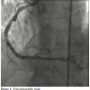

Coronary angioplasty was performed using a 7 Fr Amplatz Left I guiding catheter. Although the guiding catheter was not coaxial with the vessel, it allowed advancement of a 0.014´´ Balance Middleweight guidewire (Guidant Corporation) into the vessel, which redirected the tip of the catheter into coaxial engagement with the vessel. After advancing the guidewire at the distal vessel, multiple inflations of a 2.0 mm x 15 mm balloon were performed (up to 18 atm). Although the balloon easily crossed the lesion, it was not possible to advance a 2.5 mm x 20 mm Pl-Cr everolimus-eluting stent (Promus Element) at the distal lesion, due to insufficient backup support and heavy calcification. A 0.014 mm buddy wire (BHW, Guidant Corporation) was advanced across the lesion into the distal LAD to increase support and straighten the vessel. However, the stent was still unable to pass through successfully. We elected to aid stent delivery by performing extra deep intubation using the Guideliner 6 Fr catheter (mother and child technique). Using an inflated balloon in the distal lesion as an anchor, the Guideliner was advanced into the distal vessel. The tip of this catheter passed easily through the proximal segment, protruding by 4.1 cm into the RCA and allowed successful delivery of the stent at the distal lesion without resistance (Figure 2B). The procedure was completed by implanting 2 more non-overlapping stents (3.0 mm x 20 mm and 3.0 mm x 20 mm Promus Element stent) (Figures 2C and 2D) through the Guideliner catheter at the lesions of the mid portion of the vessel. A final postdilatation of the stents with a non-compliant balloon completed the procedure with an excellent angiographic result (Figure 3).